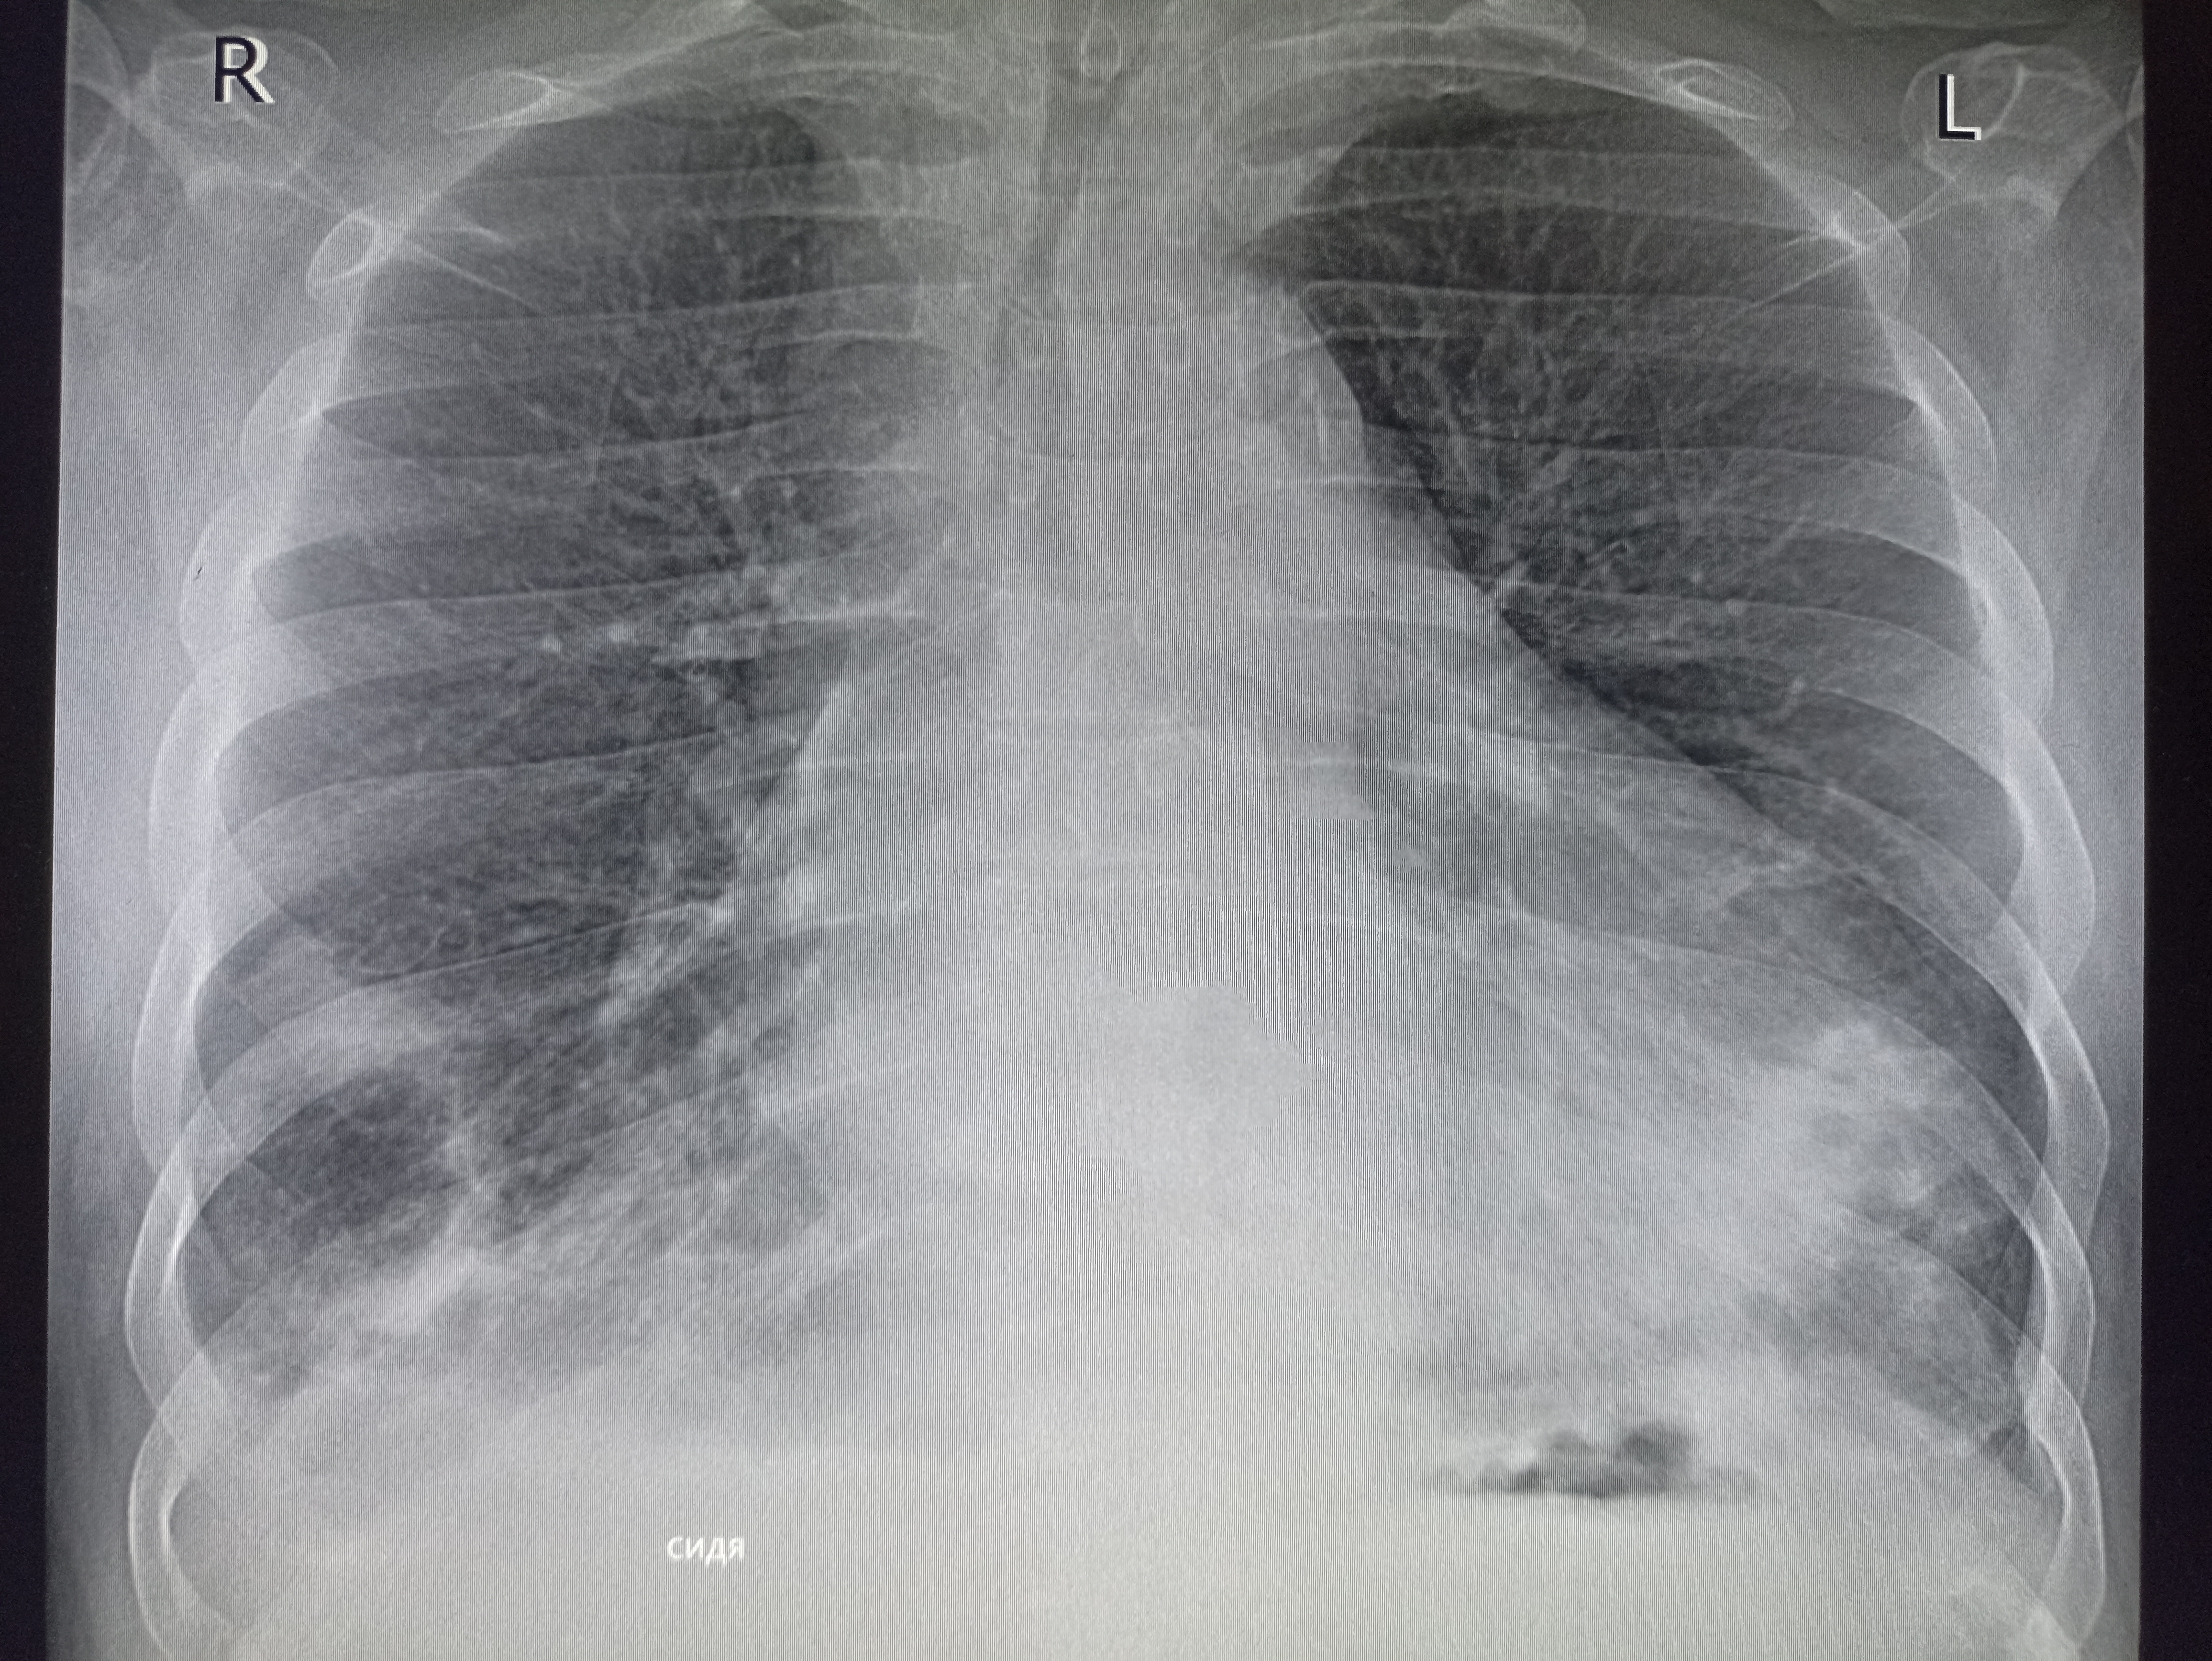

Аноним 09/12/25 Втр 07:35:09 #2 №327474821

IMG20251208112948.jpg

Где пиздецома?

>>327474821

Пневмония в нижнем сегменте.

Ну или тубер

>>327475007

Там еще жижа и плеврит

>>327475010

Бля пиздец фу гадость. Он уже лежит где-то или на своих двоих прищел?

Дренаж?

>>327475034

Пунктировали два раза уже. Приехал из поликлиники в приемник. Он там всяким по вене ставился и у него него не ток в легких все фу неоч.

Гидроторакс с линией демуазо?